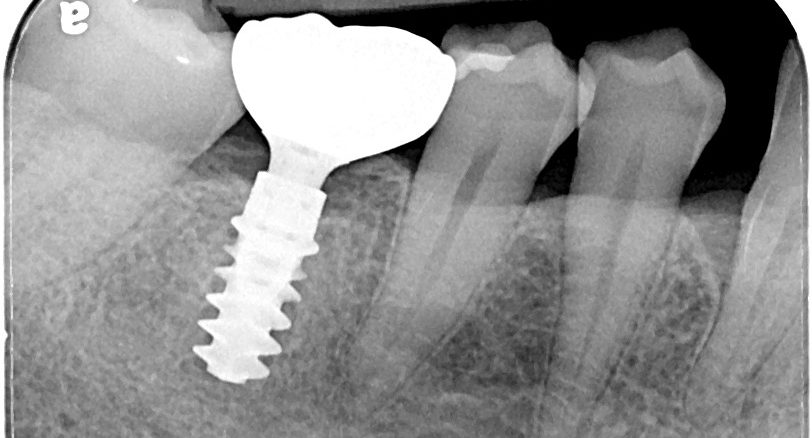

植牙手術

專科醫師親自操刀,當天裝上臨時假牙。

利用電腦模擬植牙位置,精準預測手術效果,降低風險,提升成功率。由專科醫師親自操刀,過程舒適、安全,為未來假牙打下穩固基礎。